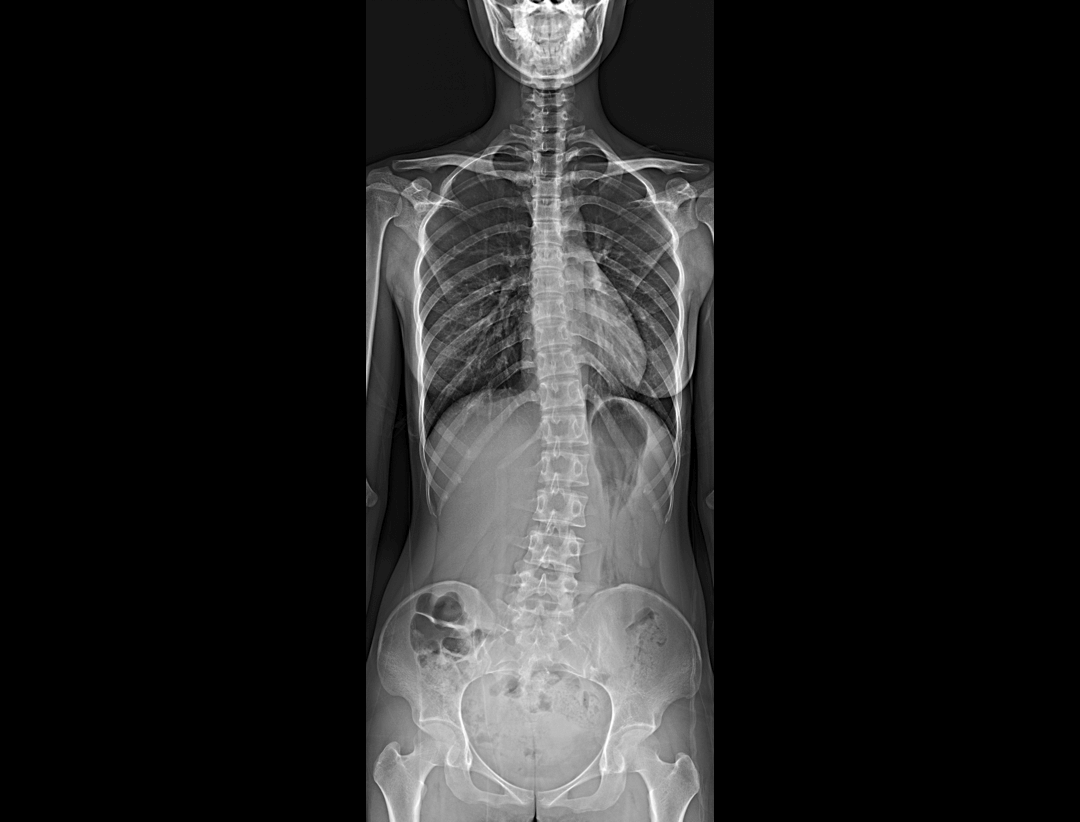

全自动无尺全景拼接*

支持自动立位无尺全景拼接,为骨科、整形外科提供高质量全景影像。

测量功能*

集成脊柱Cobb角及股骨颈干角测量功能,精准指导外科手术及术后评估。